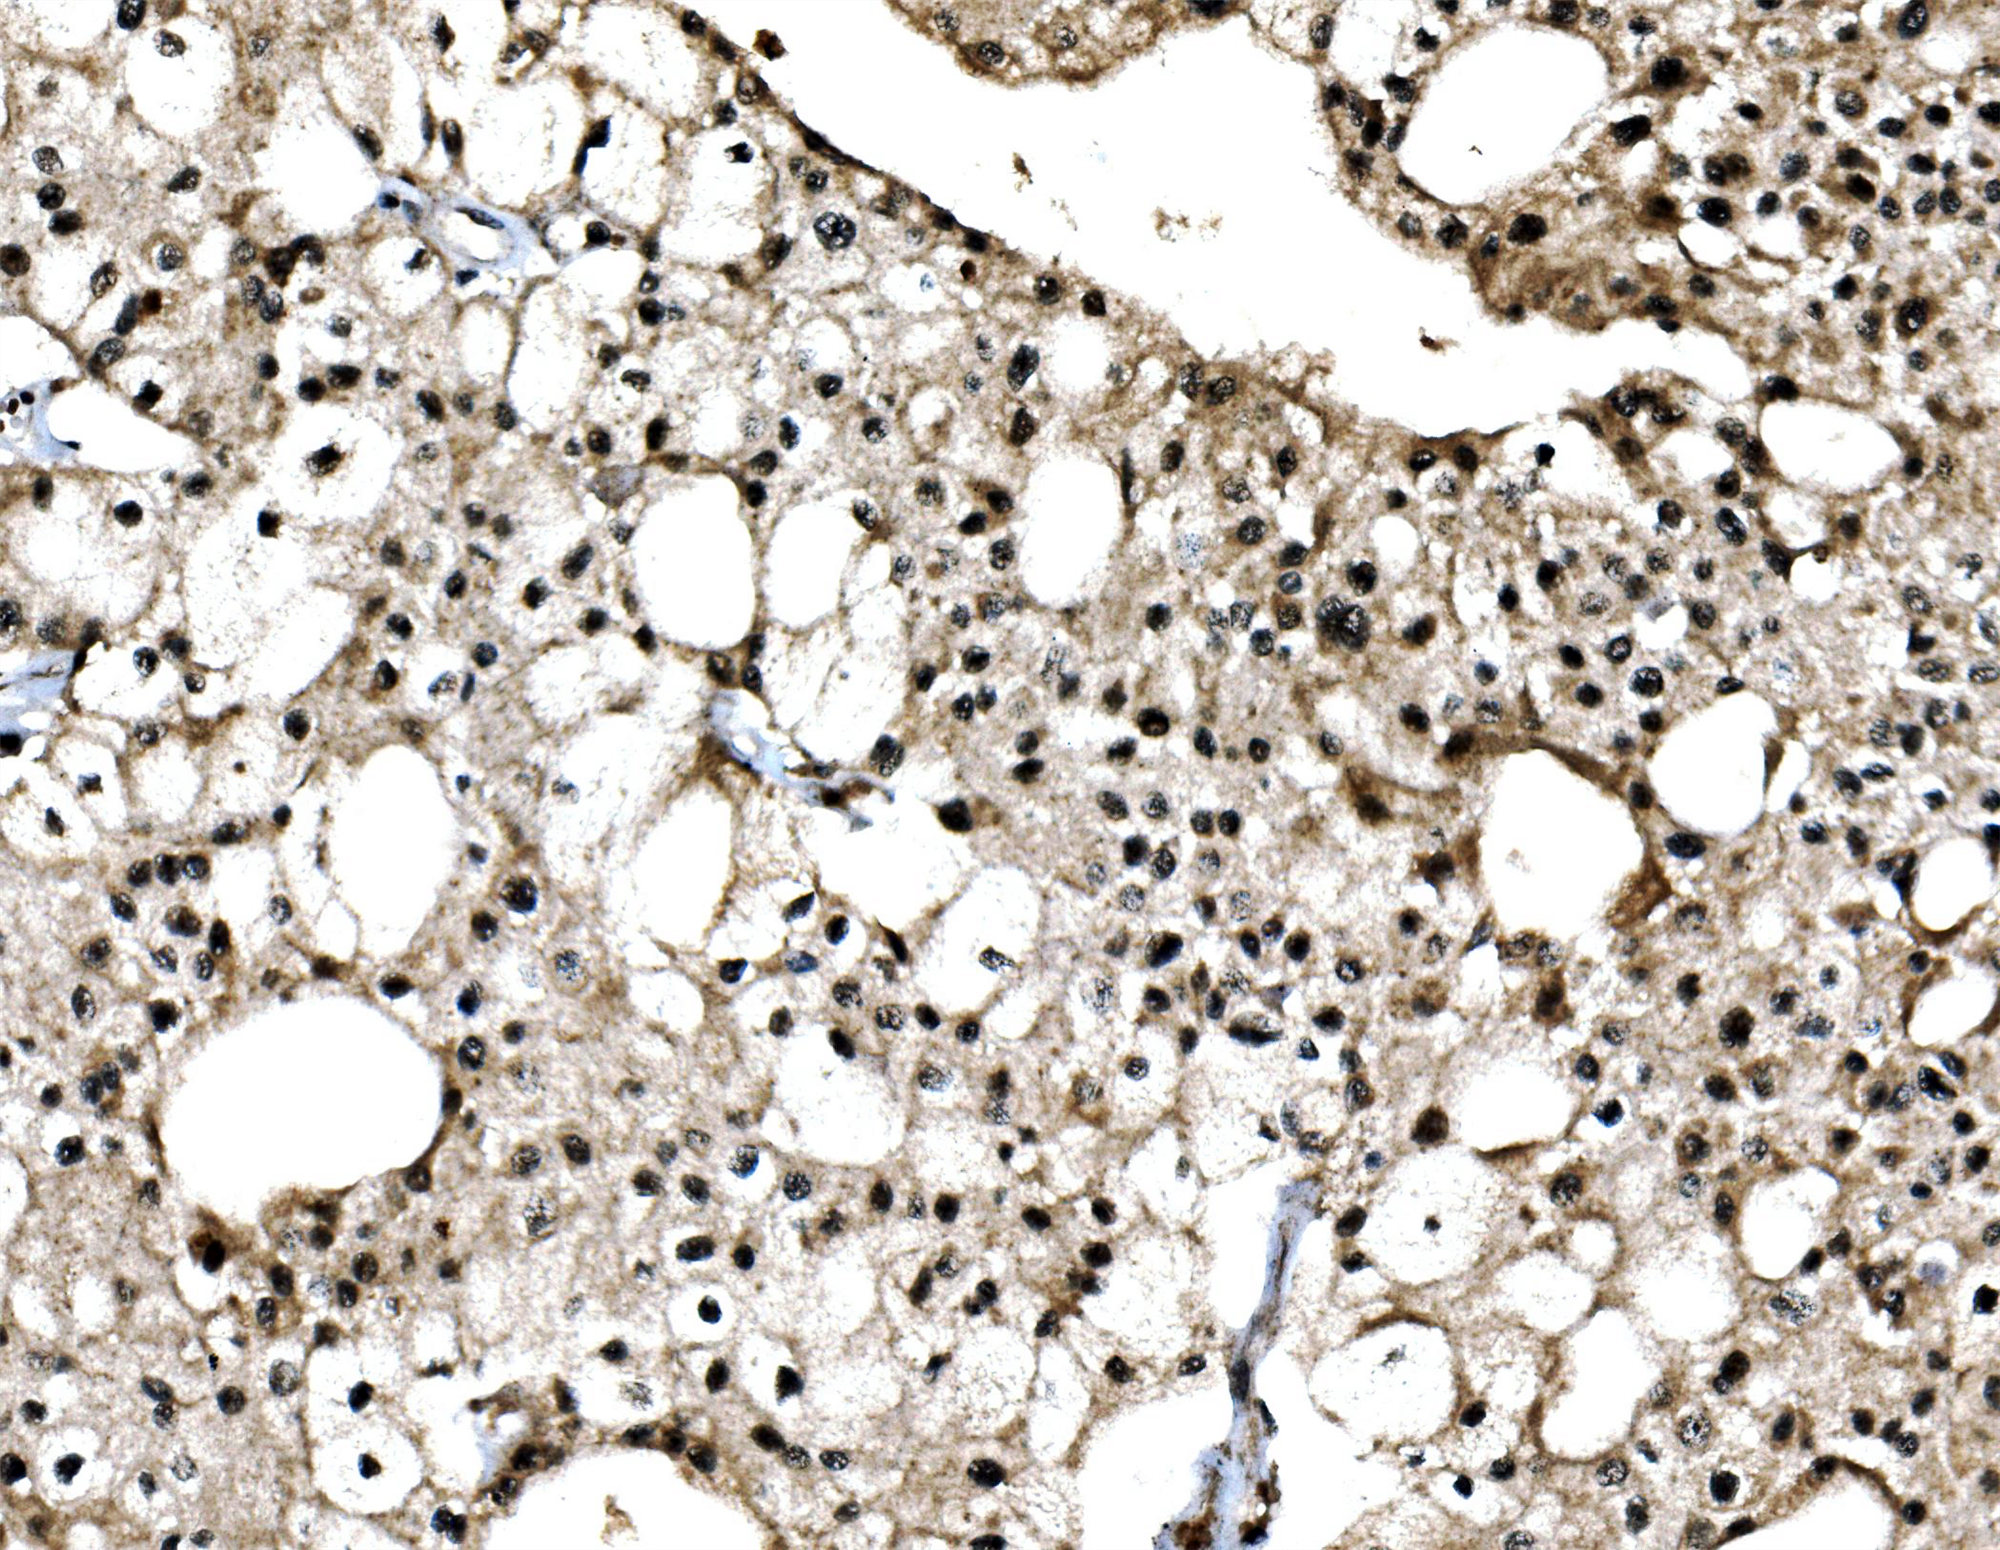

IHC analysis of c-Jun/JUN using anti-c-Jun/JUN antibody (A02038-3).

c-Jun/JUN was detected in a paraffin-embedded section of human renal cell carcinoma tissue. Biotinylated goat anti-rabbit IgG was used as secondary antibody. The tissue section was incubated with rabbit anti-c-Jun/JUN Antibody (A02038-3) at a dilution of 1:200 and developed using Strepavidin-Biotin-Complex (SABC) (Catalog # SA1022) with DAB (Catalog # AR1027) as the chromogen.